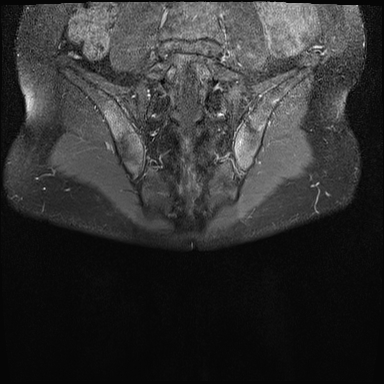

MRI

MRI chuỗi xung T1W sau tiêm thuốc tương phản từ của cùng bệnh nhân cho thấy bờ khớp cùng chậu không đều do bào mòn.

Có ngấm thuốc ở xương dưới sụn và phù nề tủy xương.

Không có tràn dịch khớp.

Thuốc tương phản từ tiêm tĩnh mạch không nhất thiết phải sử dụng để chẩn đoán viêm khớp cùng chậu.

Cuộn qua các hình ảnh MRI và so sánh với các dấu hiệu trên X-quang (hình ảnh cuối cùng).